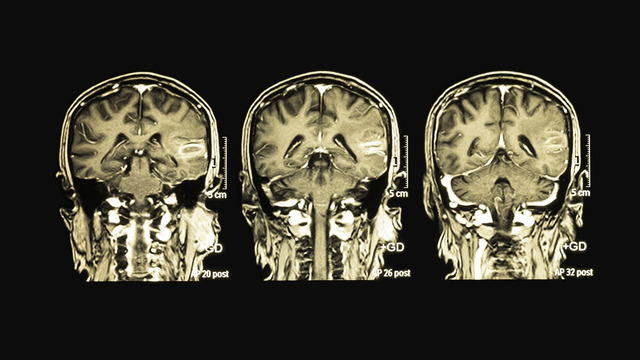

他指出,目前許多人每日久坐時間可達數小時以上,部分甚至超過10小時,長期下來可能對腦部結構造成影響。根據國際研究機構范德堡大學醫學中心(Vanderbilt University Medical Center)進行為期7年的追蹤研究顯示,長時間久坐與腦部記憶區域海馬迴(hippocampus)萎縮存在關聯。

在症狀方面,專家指出,腦部功能下降可能出現記憶力減退、專注力不足等情形。隨著人口老化與生活型態轉變,失智症與阿茲海默症(Alzheimer’s disease)案例已有增加趨勢,未來影響程度仍有待觀察。